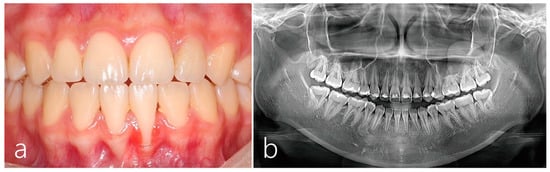

2. Case Report